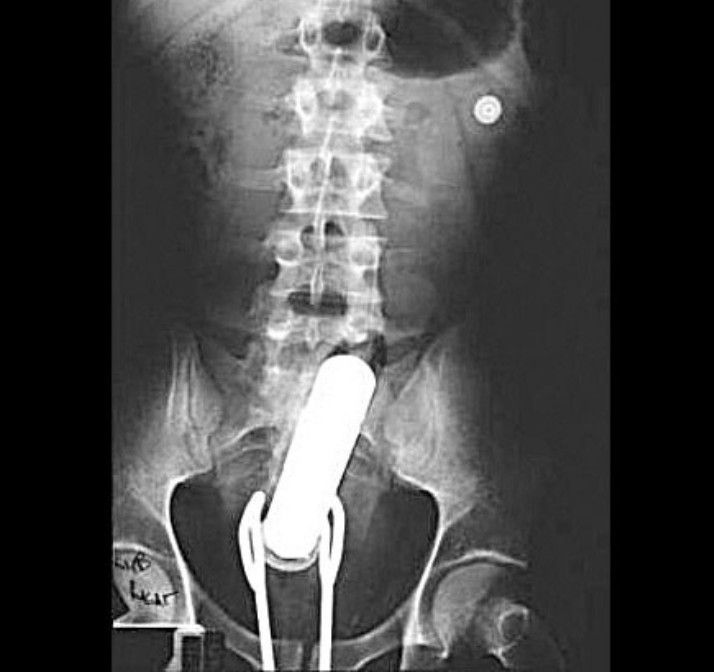

A curious finding in GI tract

A curious finding in GI tract could be seen in this radiograph.